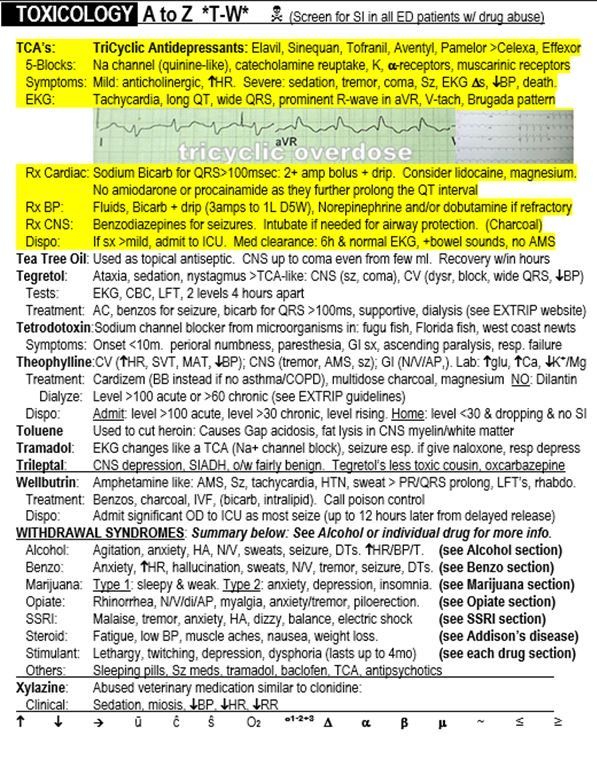

Case Report 52 year old Lethargic Woman With Nystagmus